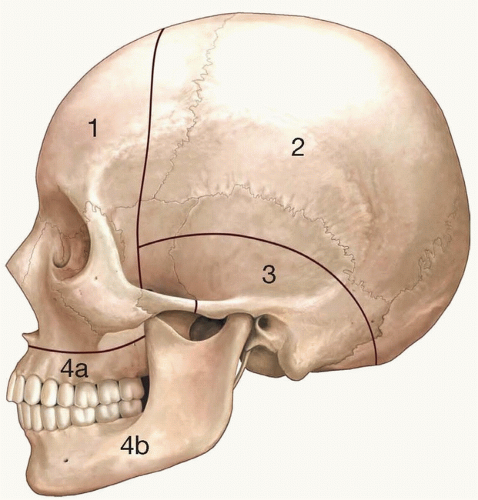

Chen et al. classified the craniomaxillofacial region into four major zones based on anatomic location, structures involved, surgical access, importance of reconstruction, and recommended treatment methods (FIG 1).6

Zone 1: Includes the frontal, nasal, ethmoidal, and zygomatic bones as well as the superior, non-tooth-bearing portion of the maxillary bone

Zone 2: Parietal, occipital, and squamous portion of the temporal bones

Zone 3: Petrous portion of the temporal bones including the mastoid process and the sphenoid bone

Zone 4: Tooth-bearing portion of the maxillary bone and the mandible and is separated into zones 4a and 4b